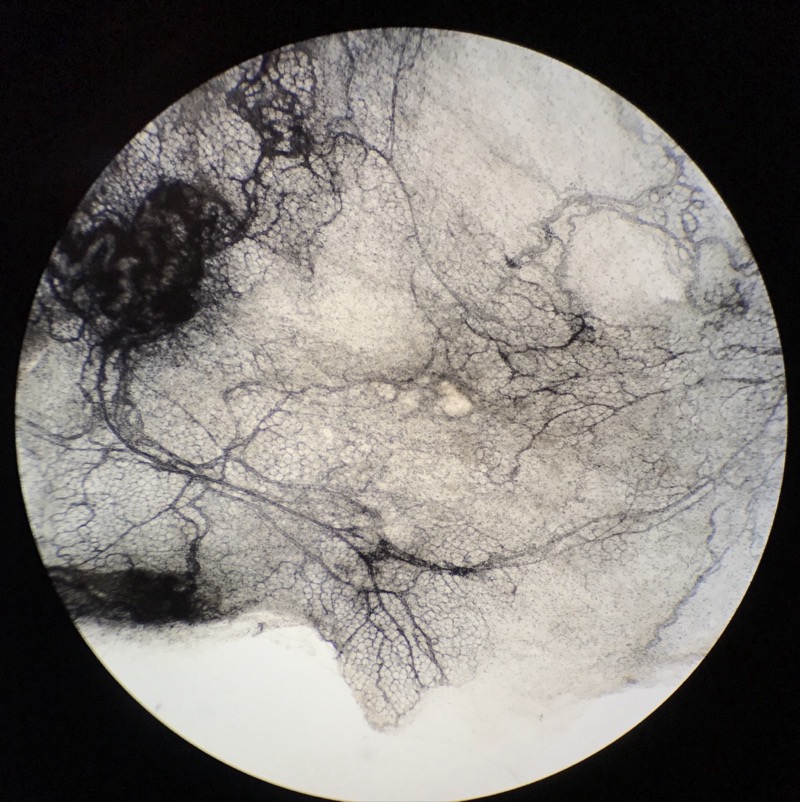

| 1:2:1 | Mesenterie, Järn-Htx | ![]() ![]() |